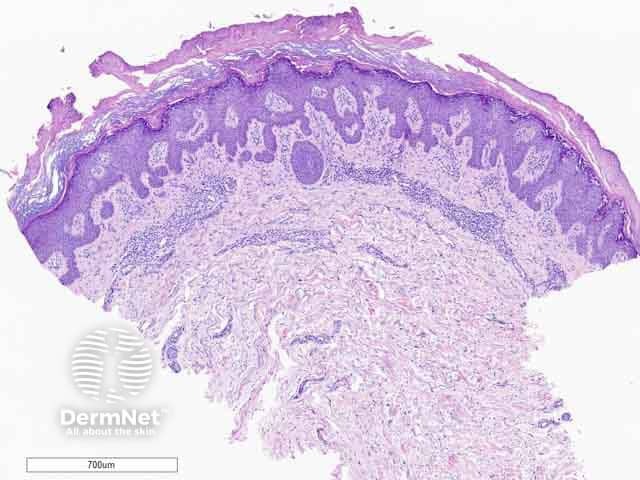

Hypergranulotic dyscornification is reminiscent of verruca vulgaris. The lesion may be exoendophytic (figure 1). There are finger-like projections of epidermal hyperplasia and hypergranulosis with clustered keratohyalin granules. The entire lesion shows compact orthokeratosis underneath a laminated and basket-weave stratum corneum (figure 2). The key feature is the corneocytes in the stratum corneum which appear rounded, glassy, and eosinophilic (figures 3–6). Parakeratosis is also usually present. There is a variable underlying inflammatory lymphocytic infiltrate in the upper dermis.

Figure 1: low power